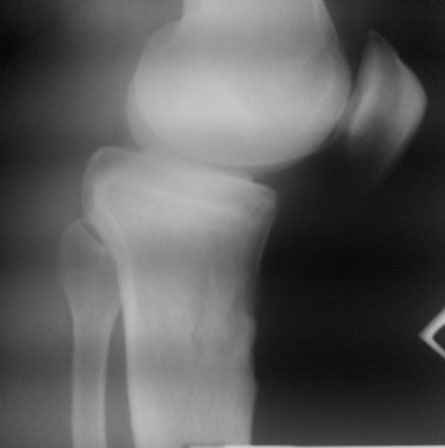

Уважаемый доктор Зайцев! Причина деформации проксимальной тибии у Вашего пациента - преждевременное и несимметричное закрытие зоны роста передней части проксимальной ростковой зоны б/б кости в следствии окультной травмы произошедшей в возрате 10-12 лет. Есть 2 причины рекурвационной деформации в области коленного сустава - мягкотканевая и костная.В данном случае Вы имеете дело не с рукурвацией коленного сустава, а с рекурвационной деформацией проксимальной голени. "Заднего выдвижного положения" на самом деле нет.То, что Вы видите на боковом снимке - это не задний подвывих голени - это снимок, сделанный в сгибании коленного сустава. Дело в том, что костные дефорсации в области коленного хорошо компенсируются за счёт движения в суставе. поэтому то, что вы видите, как задний подвывих на самом деле - сгибательное положение колена.

Это можно проверить очень просто - надо сделать стресс рентгенограмму в положении полного разгибания коленного сустава.Для этого посадите больного на стул, пятку поставьте на другой стул, дайте пациенту кассету 30Х40 держать с наружной стороны колена, и попросить ренгентехника сделать латеральный снимок с втутренней стороны. Сделав снимок здорового колена, Вы сможете расчитать деформацию.

10.-Рассмотрим представленную деформацию в боковой рентгенологической проекции.

Несложные расчеты на изготовленной скиаграмме (см. рис.1 ) показывают ,что суставная поверхность проксимального отдела б/б кости, находится в положении сгибания примерно 30 гр. Плоскость деформации лежит в сагитальной плоскости. Истинный угол деформации равен примерно 15 гр., с вершиной на 4-4.5 см. (примерно) дистальнее края суставной поверхности.

Вам представленна склаграмма боковой R – гр болного вынесенного на обсуждение.

А – ось бедра.

Б – линия Blumensaat/

В – имеющаяся линия суставной поверхности б/б кости.

Г – положение суставной поверхности в норме, по отношению к продольной оси б/б кости.

Д – продольная ось голени.

86 гр. (Г-Д) отношение суставной полверхности к оси голени.

~ 30 гр. – положение сгибания.